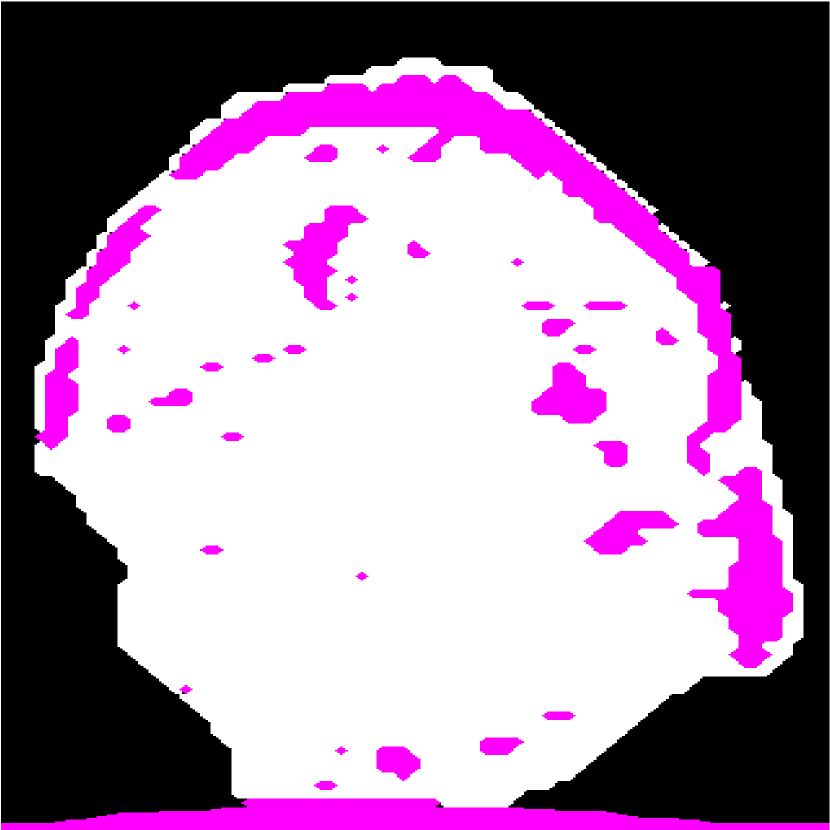

Figure 2: (a) Target HFU image. (b) Manual-segmentation result. (c) The segmentation result obtained by NGC with depth-dependent profile.

Intensity-distribution estimation is another challenge in LN segmentation. To obtain satisfactory segmentation, accurate intensity distributions for the three components of isolated LNs are required. Some clustering algorithms, such as K-means or expectation maximization (EM), may be able to categorize the intensity values of all voxels into three distributions to represent target objects. However, these approaches often yield unsatisfactory segmentation results for larger LNs (Figure 1(c)), where the intensity distribution fluctuates significantly with depth because of acoustic attenuation and focusing effects. In addition, attenuation effects may become so extreme that fat boundaries become invisible. (See the red arrow in Figure 1(a).) To mitigate the attenuation and missing-boundary problems, we used depth-dependent intensity profiles to model the depth-dependent variation of intensity mean and standard deviation in our prior work [11]. Using an expectation-maximization (EM) -based iterative framework, depth-dependent profiles were estimated by a spline-based fitting process from the previous segmentation result, and the segmentation result was obtained by NGC using the estimated depth-dependent profiles. Instead of using an EM-based framework to update profiles, level-set-based approaches can also update profiles during deformation. Bui et al. developed a method, which applied depth-dependent profiles, called statistical transverse slice level-set (STS-LS) [15]. Nevertheless, depth-dependent profiles are unable to deal with intensity inconsistency within the same depth caused by inhomogeneous acoustic attenuation as shown in Figure 2. Figure 2(c) shows the segmentation result obtained using a depth-dependent profile [11]. Compared to the manual segmentation result in Figure 2(b), some fat regions (red arrow) are mislabeled as LNP because the fat on the right (green arrow) at the same depth is much brighter than the fat on the left. In this case, depth-dependent profiles are unable to model the intensity variations accurately. Using local distribution to differentiate LNP and the fat can solve the error caused by intensity inconsistency within the same depth. Bui et al. has used a local-region-based, gamma distribution to segment LNs [13]. Level-set-based methods is good in applying local intensity distributions to differentiate regions. Since level-set-based methods deform the contour gradually, the local distributions can be updated by the boundary accordingly. However, updating distributions in local regions is computationally expensive. Furthermore, using local-region-based distributions with level-set-based methods is likely to result in convergence to a local minimum when the image is noisy. In contrast, GC-based approaches generally set the similarity cost by predefined intensity distributions. Because the boundary is unknown, the local region is hard to be determined in advance.

In the proposed framework, we apply GC-LAE in two rounds. In the first round, GC-LAE is applied with the local adaptive energy only. The top row in Figure 7 shows the segmentation results of GC-LAE obtained by several different k𝑘k in the first round. Because the contrast between LNP and the fat at left hand side (green arrow) is low, GC-LAE may segment some LNP voxels as the fat region when k𝑘k is small or segment all voxels as LNP when k𝑘k is high.

As demonstrated, there is not a single value for k𝑘k that will work well in all regions. Therefore we apply GC-LAE with several different k𝑘k values, and then fuse the results. The automatic selection of up to three k values is described in Sec. III-D. We use the intersection of the LNP regions obtained with different k𝑘k as the confident region for LNP (white region in Figure 7(a) bottom), and we use the intersection of the fat regions as the confident region for fat (pink region in Figure 7(a)). From these confident regions, we determine the mean and STD of LNP and the fat at different depths. To suppress the noise in the resulting mean and STD values, we further fit the mean and STD profiles along the depth into two separate spline functions using the spline-based approach with RANSAC [22].

In the second round, GC-LAE is applied with local adaptive-energy term and the global energy term (Eq. (2)). The global energy is defined by the depth-dependent profiles obtained from the confident regions in the first round. The bottom row of Figure 7 shows the segmentation results of GC-LAE with global energy which have more accurate boundary on the left. Similar to the first round of GC-LAE, we can fuse these results to obtain new confident regions for both LNP and fat, and derive the new depth-dependent mean and STD profiles.